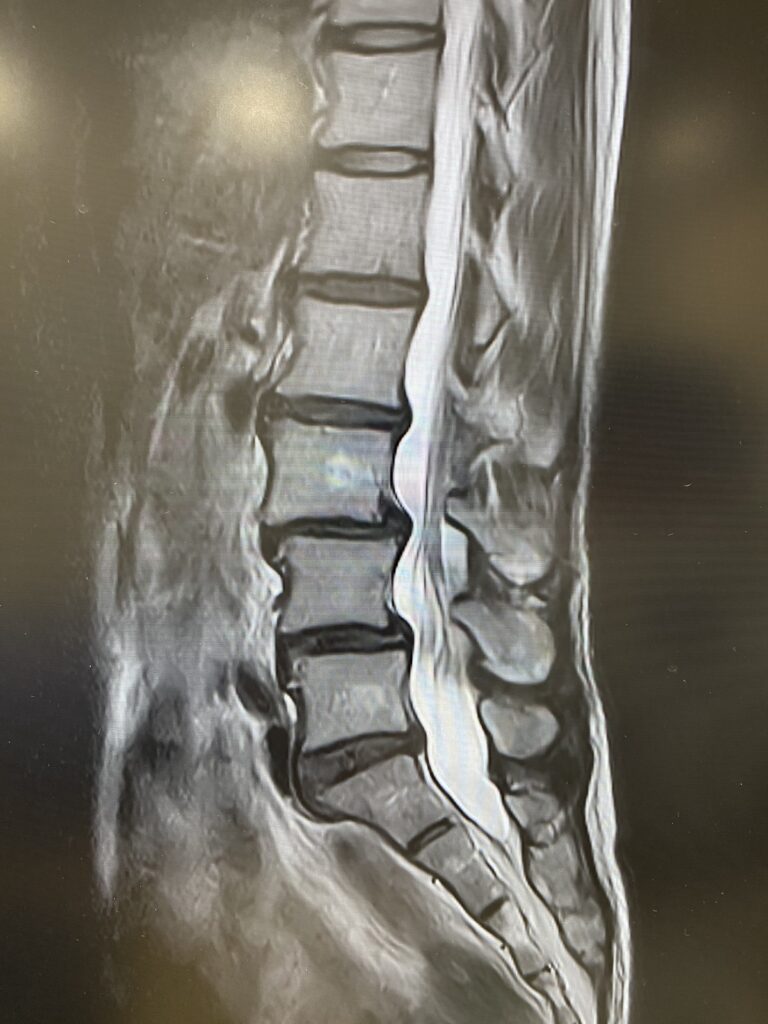

1.5T MRIへの更新作業が完了しました。

9月上旬から休止していたMRIの撮影が可能となり、画像精度が飛躍的に向上します。